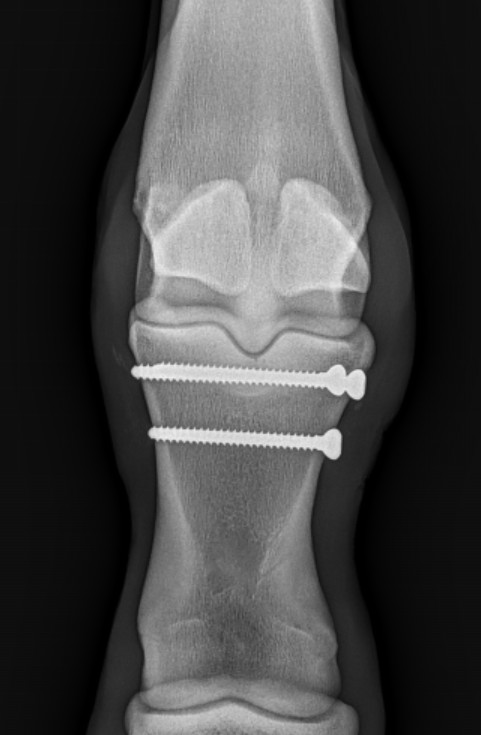

This 4-wk old STB filly was born with a marked varus (‘turned in’) deformity of her RH ankle and needed a little help🔩🪛By placing a temporary screw on the side of the growth plate with the disparate growth we can slow that side down while the other side catches up! In 2-3 weeks